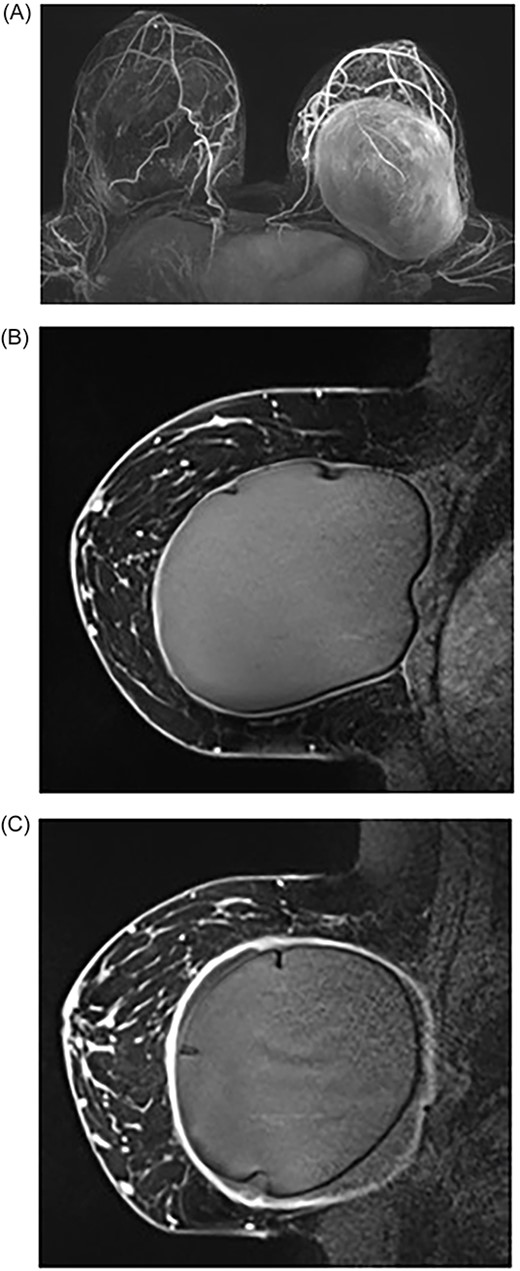

We report a total of three patients who presented with mastalgia and breast swelling following breast implants with histopathological confirmation of C. acnes. The mean age was 32 (±7.5) years. The average implant age was 8 (±1.8) years ranging from 6 to 10 years. The average onset of symptoms before presentation to a surgeon was 18 months (±21) ranging from 1.5 to 48 months. The common symptoms included breast swelling and mastalgia. All patients had bilateral capsulectomy with the removal of implants (Fig. 2). All patients had resolution of symptoms with a minimum of 1-year follow-up without complications.

Intraoperative photos of bilateral breast implants. (A) Patient 1: right and left breast implant capsules. (B) Patient 2: right and left breast implant capsules. (C) Patient 3: right and left breast implant capsules

Breast MRI demonstrated disruptions in the silicone-matrix of both breast implants. There was no abnormality of concern to suggest BIA-ALCL and no features of breast carcinoma or adenopathy. The patient underwent the removal of bilateral breast implants with an en bloc capsulectomy and bilateral corrective mastopexy. Intraoperative findings revealed that both implant capsules significantly adhered to the ribs, muscles and implants contained thick peri-implant fluid bilaterally suspicious for a gel bleed (Fig. 2). There was significant peri-implant fibrotic scar tissue and adhesions with no extra-capsular siliconoma or mass seen with no features of ALCL. Histopathological analysis demonstrated a benign fibrous capsule with synovial metaplasia with no atypical lymphoid infiltrate present; cultures from the both capsules grew C. acnes.